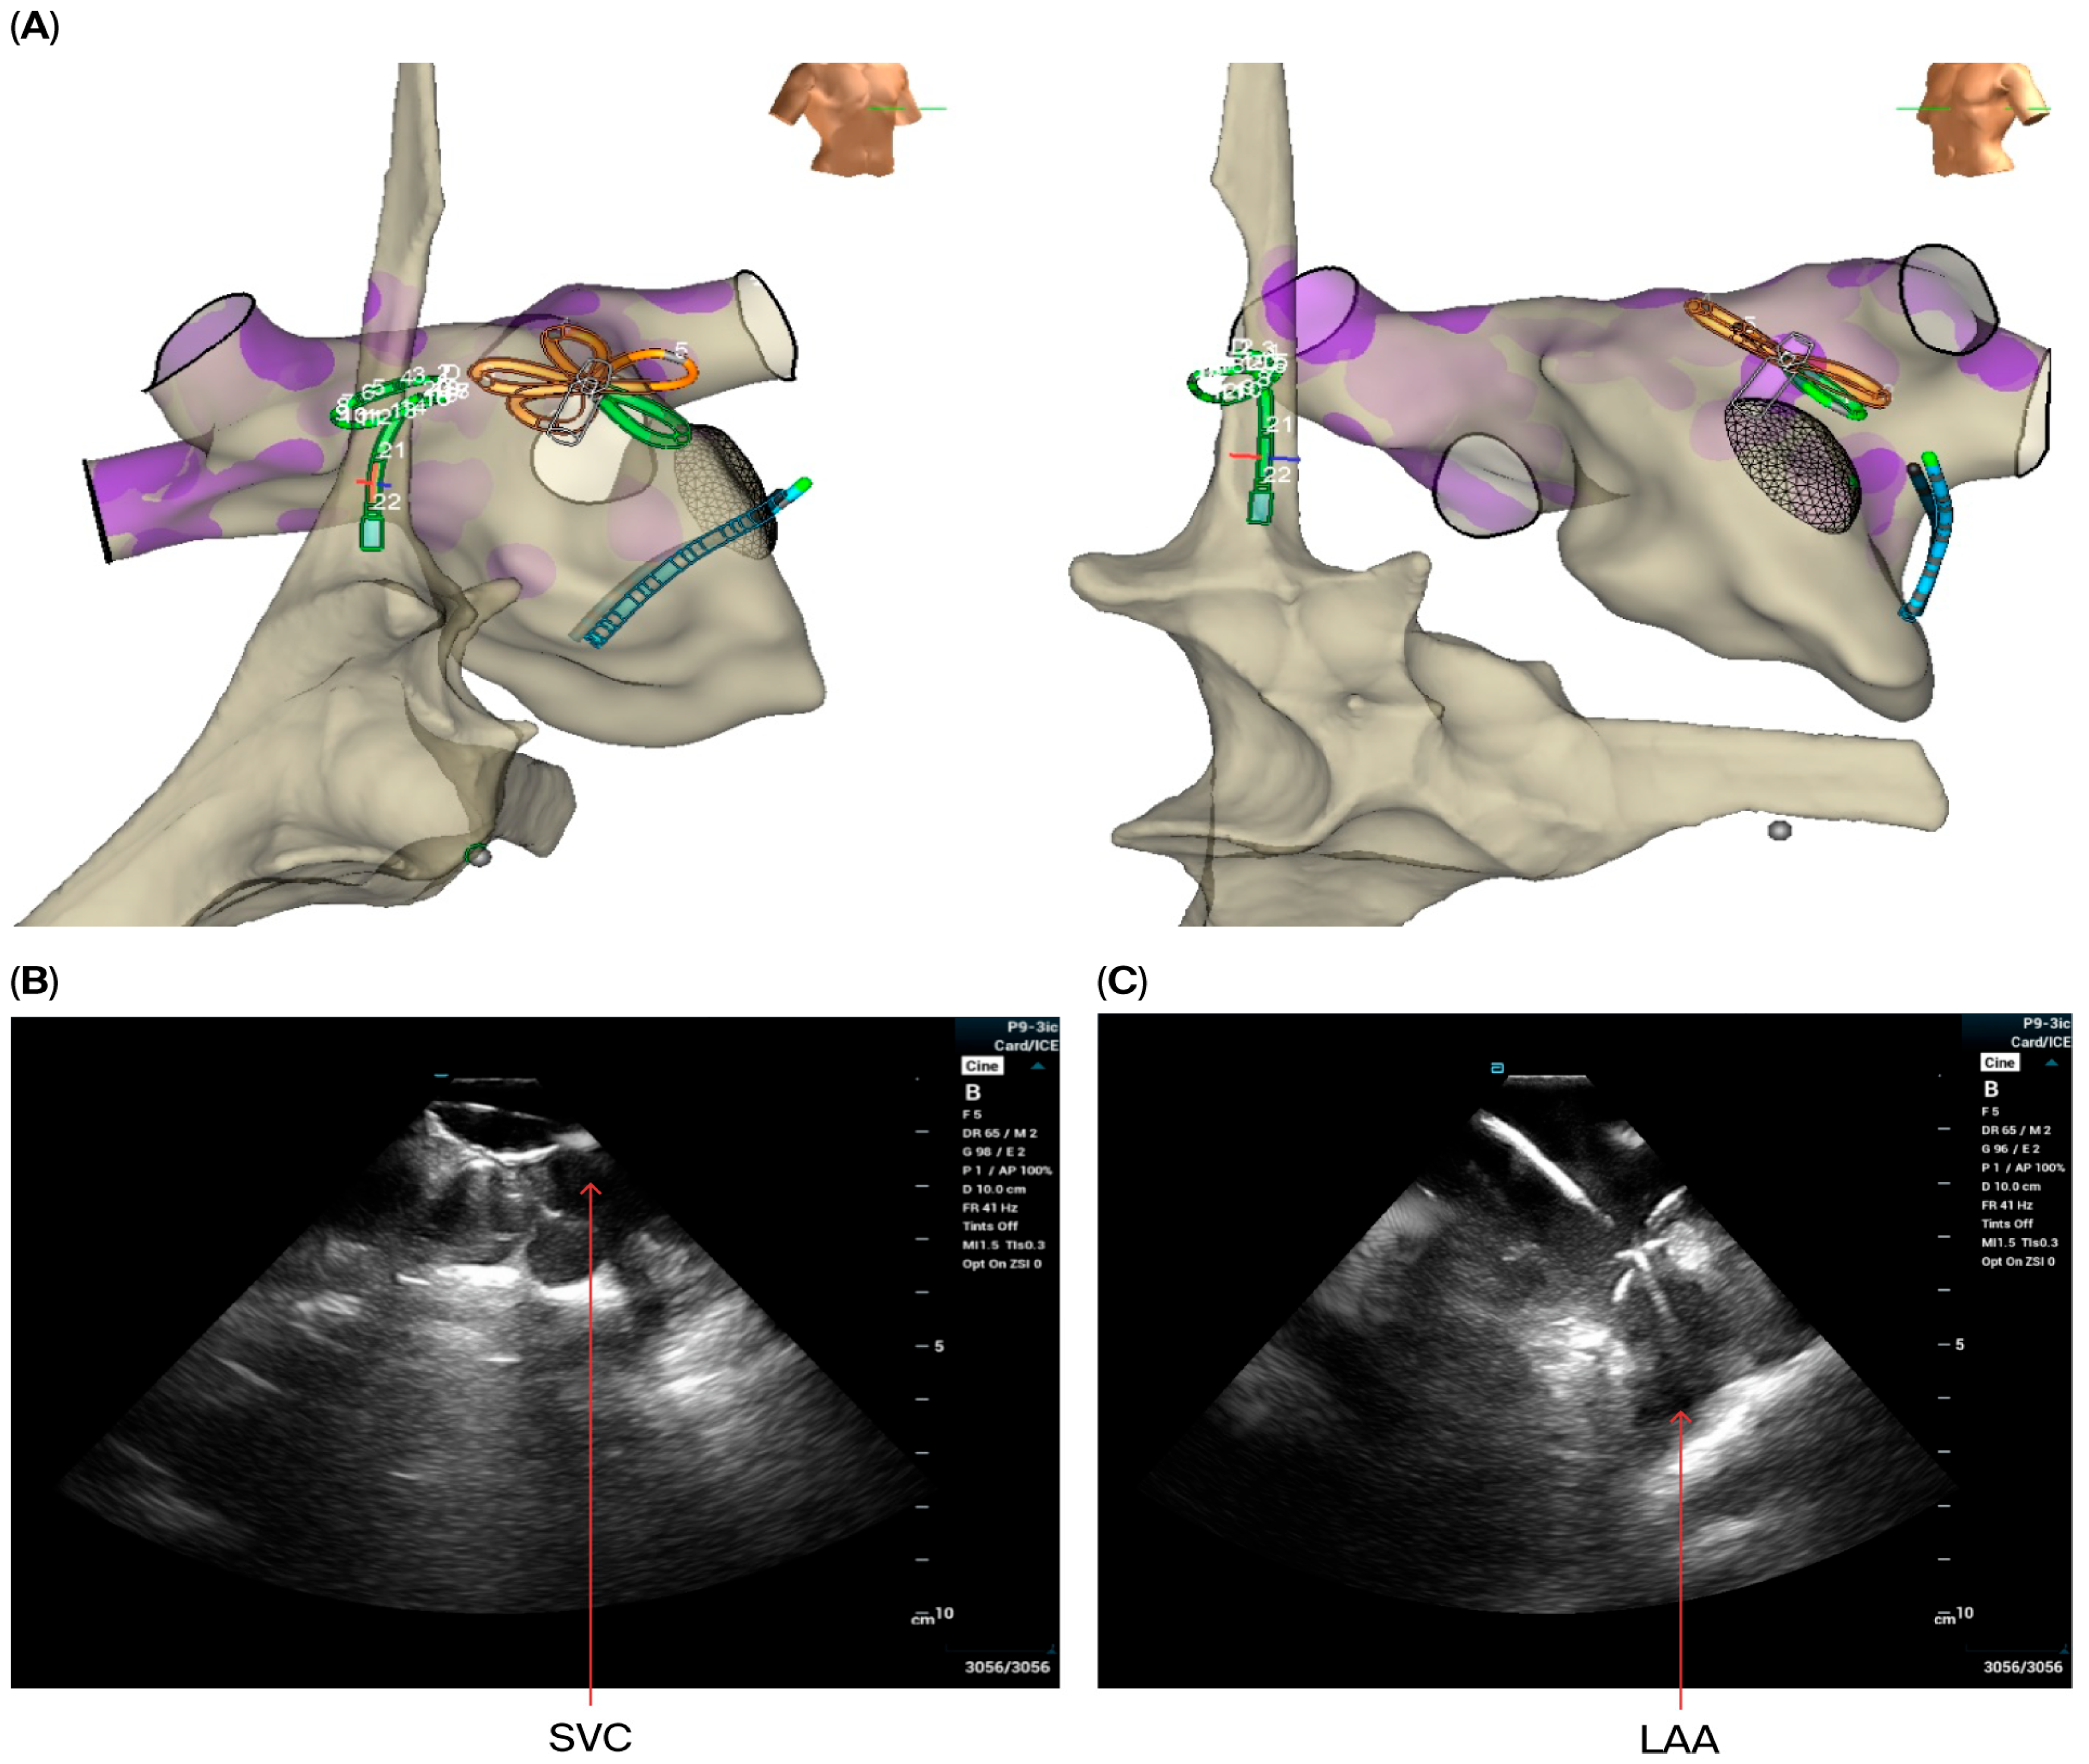

- Via the access in left femoral vein, the ICE catheter was advanced to the RA and the decapolar catheter was advanced to the coronary sinus. Baseline ICE images were obtained from the RA and then RV to assess the anatomy of the interatrial septum, LV function, and the presence of preprocedural pericardial effusion. Then, the ICE probe was advanced to the SVC to visualize the transseptal wire and sheath.

- Via the access in the right femoral vein, the VersaCross Access Solution wire (Boston Scientific, Marlborough, MA, USA) and sheath were advanced to the SVC under ICE monitoring. A single transseptal approach was performed and after crossing the septum VersaCross wire was placed in the left superior pulmonary vein, which was confirmed in ICE views from RA and from RV if needed.

- The VersaCross sheath was exchanged for the Faradrive sheath and dilatator. After predilatation of transseptal puncture, the Faradrive sheath was retracted, and the ICE catheter was advanced along the VersaCross wire to the left atrium (Figure 1A–D). Then, the Faradrive sheath was moved back to the LA, and the dilator and Versacross wire were removed, with the ICE catheter and PFA sheath placed in the LA via a single transseptal puncture.

- For superior vena cava (SVC) isolation, the ICE catheter was retracted to the top right of the atrium to guide the ablation procedure. Prior to and after ablating the SVC, the CMC was placed at the junction of the SVC and right atrium to map the phrenic nerve and to detect potential phrenic nerve injury. Then, the Pentaspline catheter was placed at the junction of right atrium and SVC (the lower edge of the right pulmonary artery level in ICE imaging). A total of 4 applications in the basket configuration were delivered (2 followed by 2 other applications after rotating the catheter 30 degree), and heart rate was monitored during the procedure.